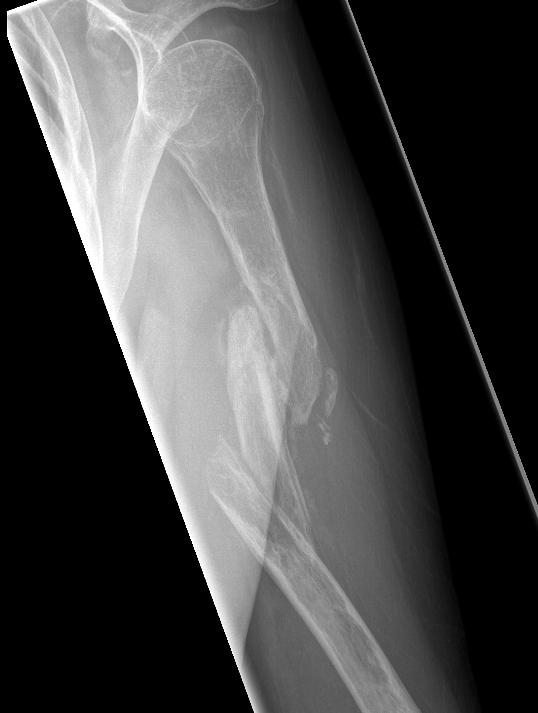

Nonunion in a proximal humerus shaft fracture treated nonoperatively